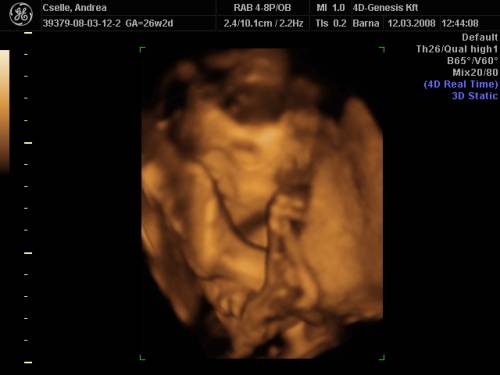

szép kis pocó!